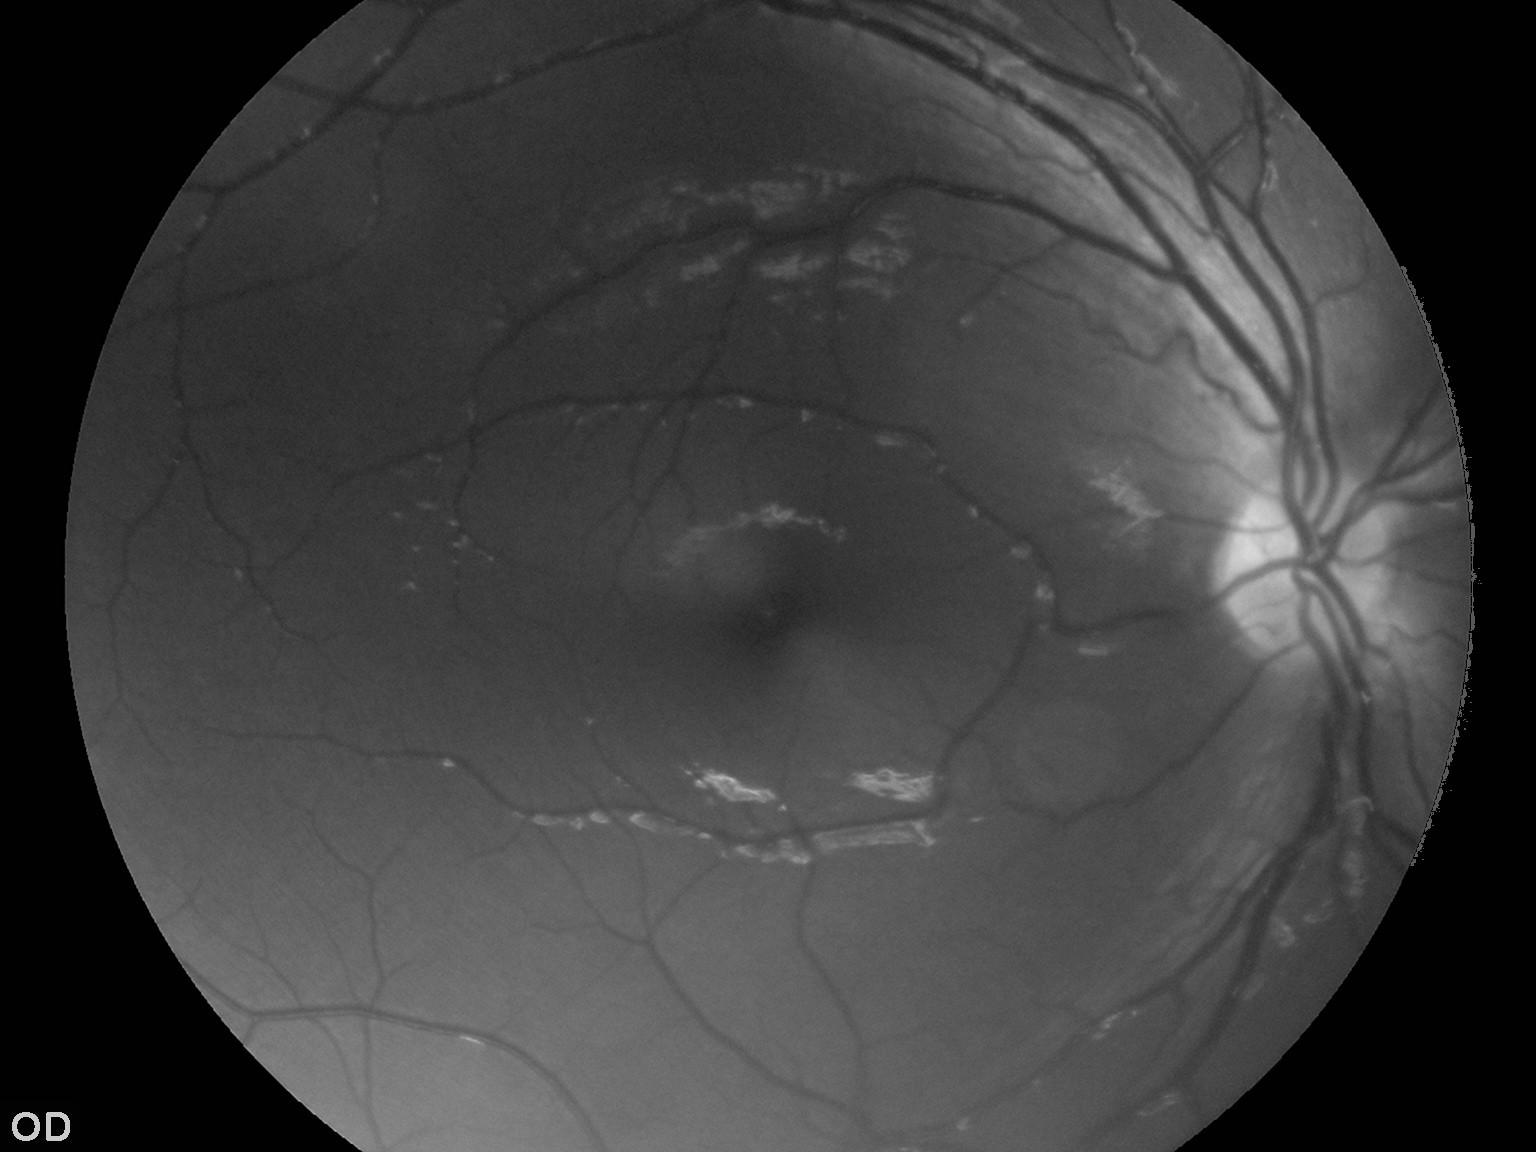

这是我试图从其中提取血管的原始图像: